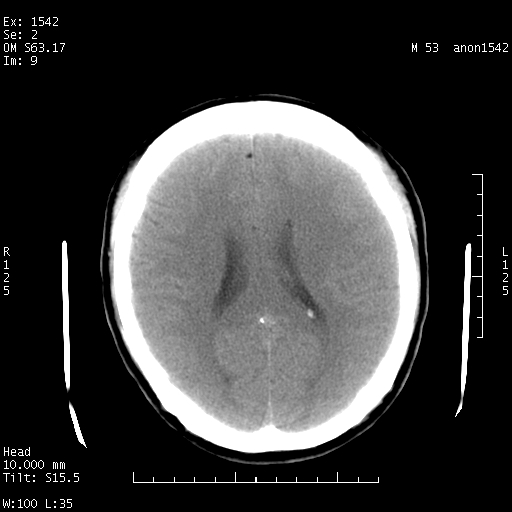

标题: CT10811:M53Y,头痛一月.其它没有什么 [打印本页]

标题: CT10811:M53Y,头痛一月.其它没有什么

左侧鞍旁不规则低密度,此区域和侧脑室有液平。若无外伤史。考虑左侧鞍旁表皮样囊肿自发破溃。

鞍旁颞叶低密度灶.其中散在空气影.还有侧脑室.是否考虑脑脓肿(请提供病史情况)

1.支持考虑左侧鞍旁表皮样囊肿自发破可能;

2.转移待排,其他?

有肿瘤样病变破溃,沿外侧裂生长,为什么不考虑胆脂瘤?

考虑左侧鞍旁表皮样囊肿自发破溃。